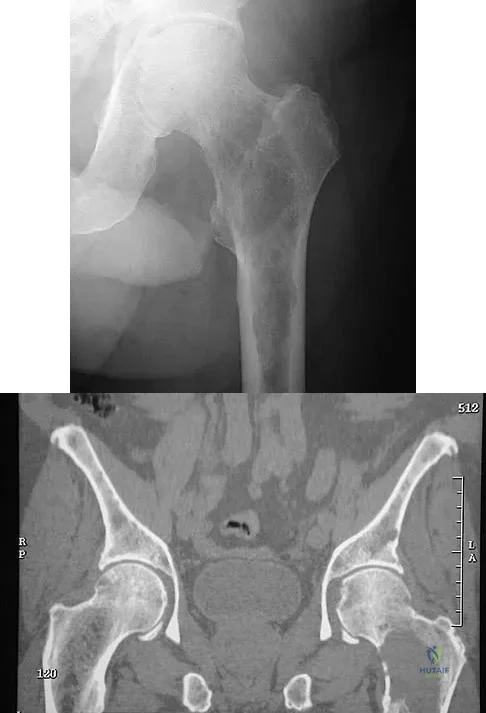

Question 18

A 47-year-old woman has had a 1-month history of left hip and medial thigh pain that is exacerbated by sitting. Laboratory studies show a total protein level of 8.2 g/dL (normal 6.0 to 8.0) and an immunoglobulin G (IGG) level of 2,130 mg/dL (normal 562 to 1,835). A radiograph, CT scan, and biopsy specimen are shown in Figures 38a through 38c. What is the most likely diagnosis?

Explanation